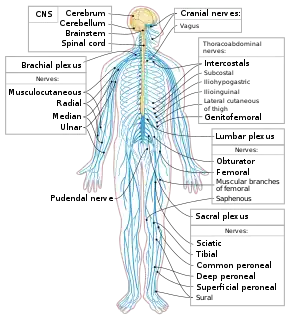

The vertebrate nervous system can be split into two parts: the central nervous system (defined as the brain and spinal cord), and the peripheral nervous system. In many species—including all vertebrates—the nervous system is the most complex organ system in the body, with most of the complexity residing in the brain. The human brain alone contains around one hundred billion neurons and one hundred trillion synapses; it consists of thousands of distinguishable substructures, connected to each other in synaptic networks whose intricacies have only begun to be unraveled. At least one out of three of the approximately 20,000 genes belonging to the human genome is expressed mainly in the brain.[40]

Neurology works with diseases of the central and peripheral nervous systems, such as amyotrophic lateral sclerosis (ALS) and stroke, and their medical treatment. Psychiatry focuses on affective, behavioral, cognitive, and perceptual disorders. Anesthesiology focuses on perception of pain, and pharmacologic alteration of consciousness. Neuropathology focuses upon the classification and underlying pathogenic mechanisms of central and peripheral nervous system and muscle diseases, with an emphasis on morphologic, microscopic, and chemically observable alterations. Neurosurgery and psychosurgery work primarily with surgical treatment of diseases of the central and peripheral nervous systems.[70]